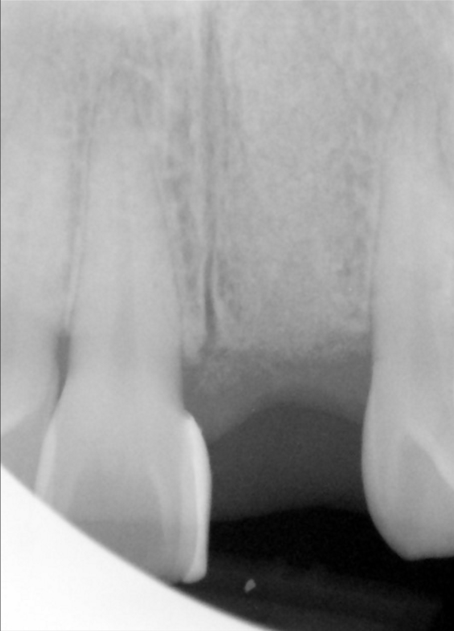

In this case a young prosector came to our office with a failing front tooth. It was removed and the area was grafted in preparation for dental implant placement.

These images show the process from bone graft, to implant placement and finally dental implant restoration.